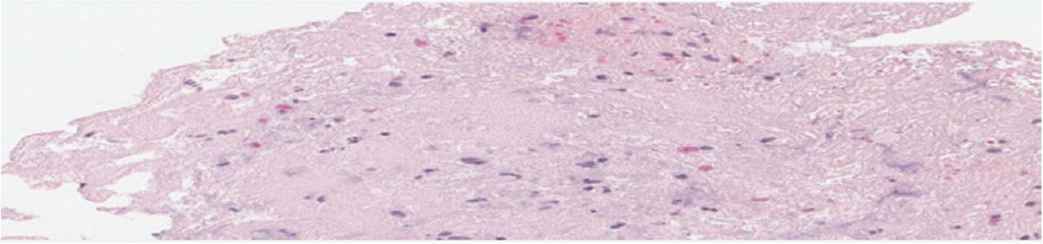

The participants consisted of men with an average age of 49.5 ± 11 years, of whom 20% had a history of coronary artery disease. The culprit vessels were right coronary artery, left anterior descending artery, and left circumflex in 48%, 44%, and 8%, respectively. There were two cardiogenic shock patients, and 44% had diabetes mellitus. The average D2B time was 127 ± 52 min. A no-reflow phenomenon was observed in 14 patients (56%). Upon histopathology study, we noticed that a predominant cleft of cholesterol was present, which may denote a high prevalence of dyslipidemia (Figure 1). The histopathology classification of thrombus based on age showed that 17 patients had recent thrombus (Figure 2), four patients had lytic thrombus (Figure 3), three patients had organized thrombus (Figure 4), two patients had no thrombus, and only patient had plaque components (Table 1). The histopathology data showed eight out of 25 patients had non-recent thrombus (32%), which implies the age of STEMI is more than 24 h despite the patients being clinically eligible for primary PCI (i.e., recorded onset of symptoms of <12 h).

Lytic thrombus (9.09%) showing homogenization of structural elements with nuclear fragmentation. Hematoxylin and Eosin (H&E), 40×.